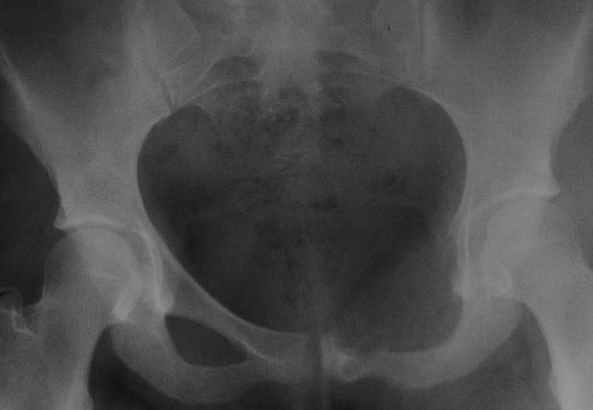

пациентка 20 лет, в сентябре 2005 года почувствовала боли в паху. На снимках заподозрили остеомиелит, лечили антибиотиками без эффекта. К онкологу попала в январе2006. Биопсия в марте 2006 - остеобластокластома. Местные онкологи от операции отказываются.

Вопрос с планом лечения (надо ли замещать деффект и чем) и где оперироваться (опыт подобных операций).В приложении рентгенограммы в динамике (2005 сентябрь, декабрь, 2006 апрель).